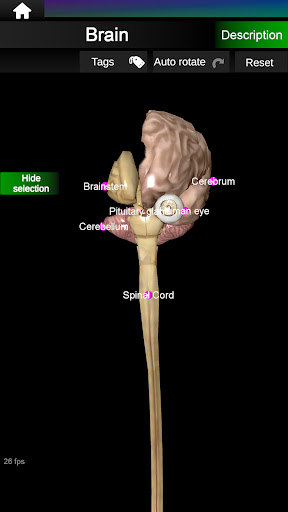

Menampilkan model anatomi 3D dari organ utama tubuh manusia dan penjelasannya masing-masing.

Apa yang ada di aplikasi?

* Otak, yang meliputi otak, otak kecil, dan batang otak.

* Mudah diakses dan dinavigasi (zoom, rotasi 3D).

* Sembunyikan atau tampilkan informasi.

* Deskripsi masing-masing organ.